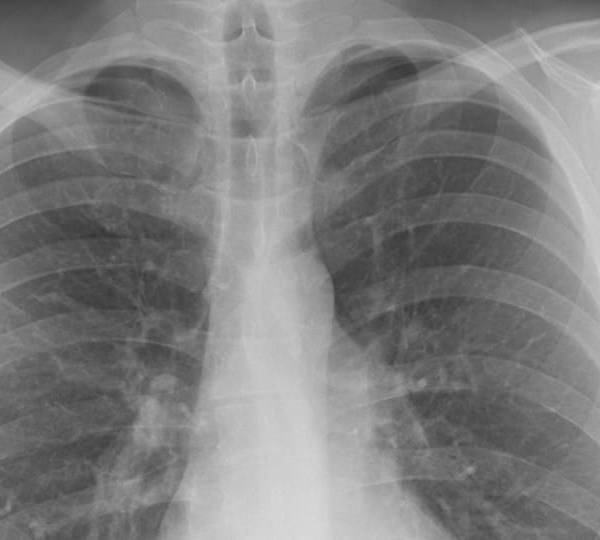

La enzima podría ser efectiva en el tratamiento del cáncer y enfermedades en los pulmones.

Los resultados de un estudio de investigación, dirigido por científicos de Henry Ford Health System (Estados Unidos) y publicados en la revista 'Nature Communications', sugieren que una enzima podría desempeñar un papel importante en el tratamiento del cáncer y las enfermedades autoinmunes en las vías respiratorias.